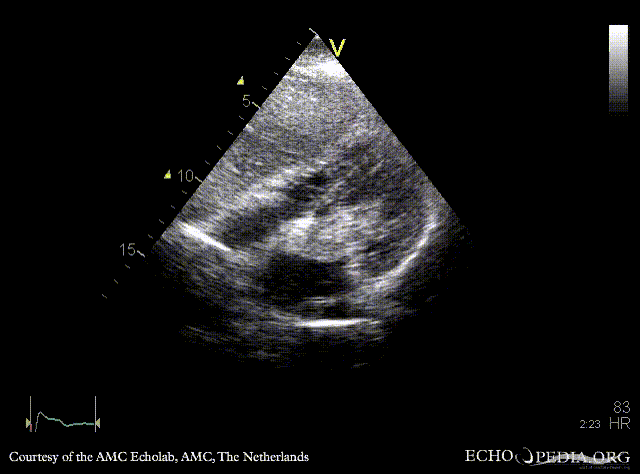

Giant myxoma in left atrium

A4CH